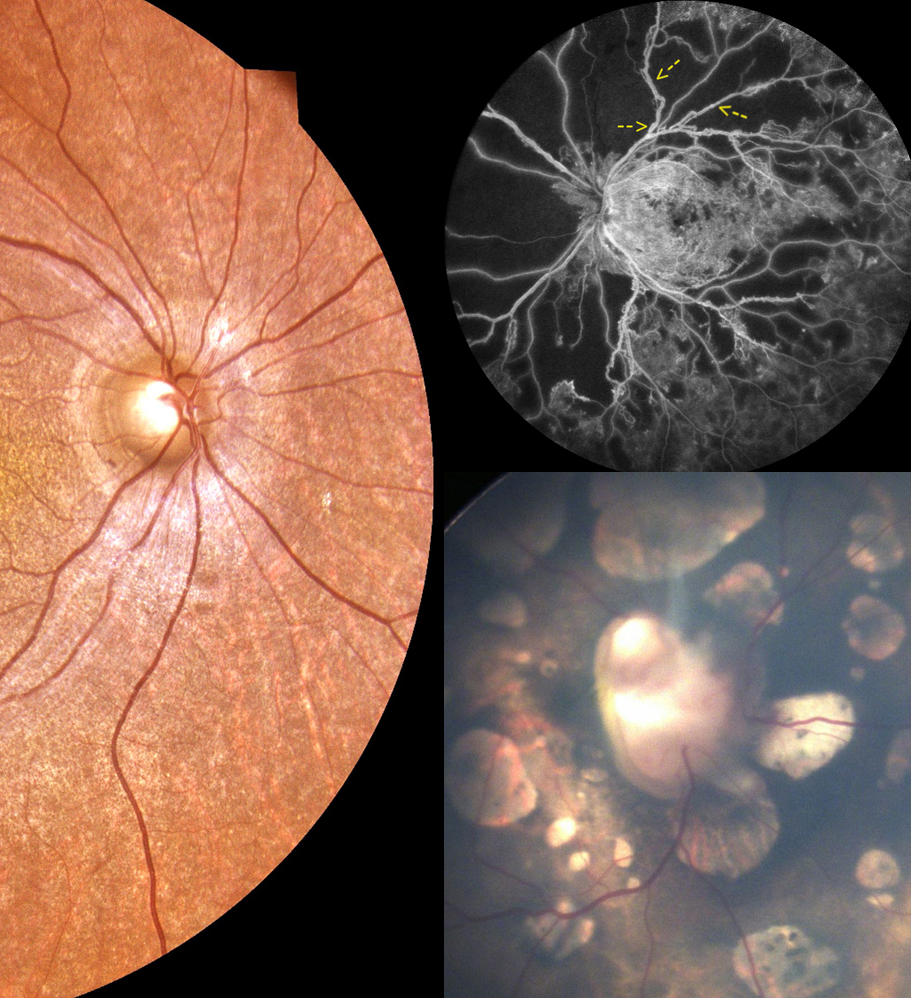

Proliferative diabetic retinopathy

Horseshoe tears in the retina after traumatic posterior vitreous detachment

A quadruple fundal coloboma

Moniliform blepharosis in lipoid proteinosis

Conjunctival ulcers: a rare feature of ocular herpes simplex virus infection

Choriretinal lacunae aid in the diagnosis of Aicardi syndrome

Pseudoexfoliative material on an intraocular lens

Bull’s eye maculopathy in a young patient with systemic lupus erythematosus

Persistent pupillary membrane type 2

Cilium incarnatum internum

Bilateral prepapillary vascular loops in a pediatric patient

Macular telangiectasia type 2 complicated with choroidal neovascularization

Anterior suprachoroidal hemorrhage abutting anterior chamber intraocular lens

Spontaneously dislocated lens with ring-shaped pigmentation